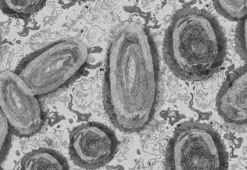

Maymun çiçeği (Monkeypox), ilk olarak 1958’de maymunlarda keşfedilen ve 1970’de insanlarda görülen nadir bir viral enfeksiyondur. Çiçek hastalığına benzer belirtiler gösteren bu virüs, Orthopoxvirus ailesine aittir ve genellikle Afrika'nın kırsal bölgelerinde yaygındır.